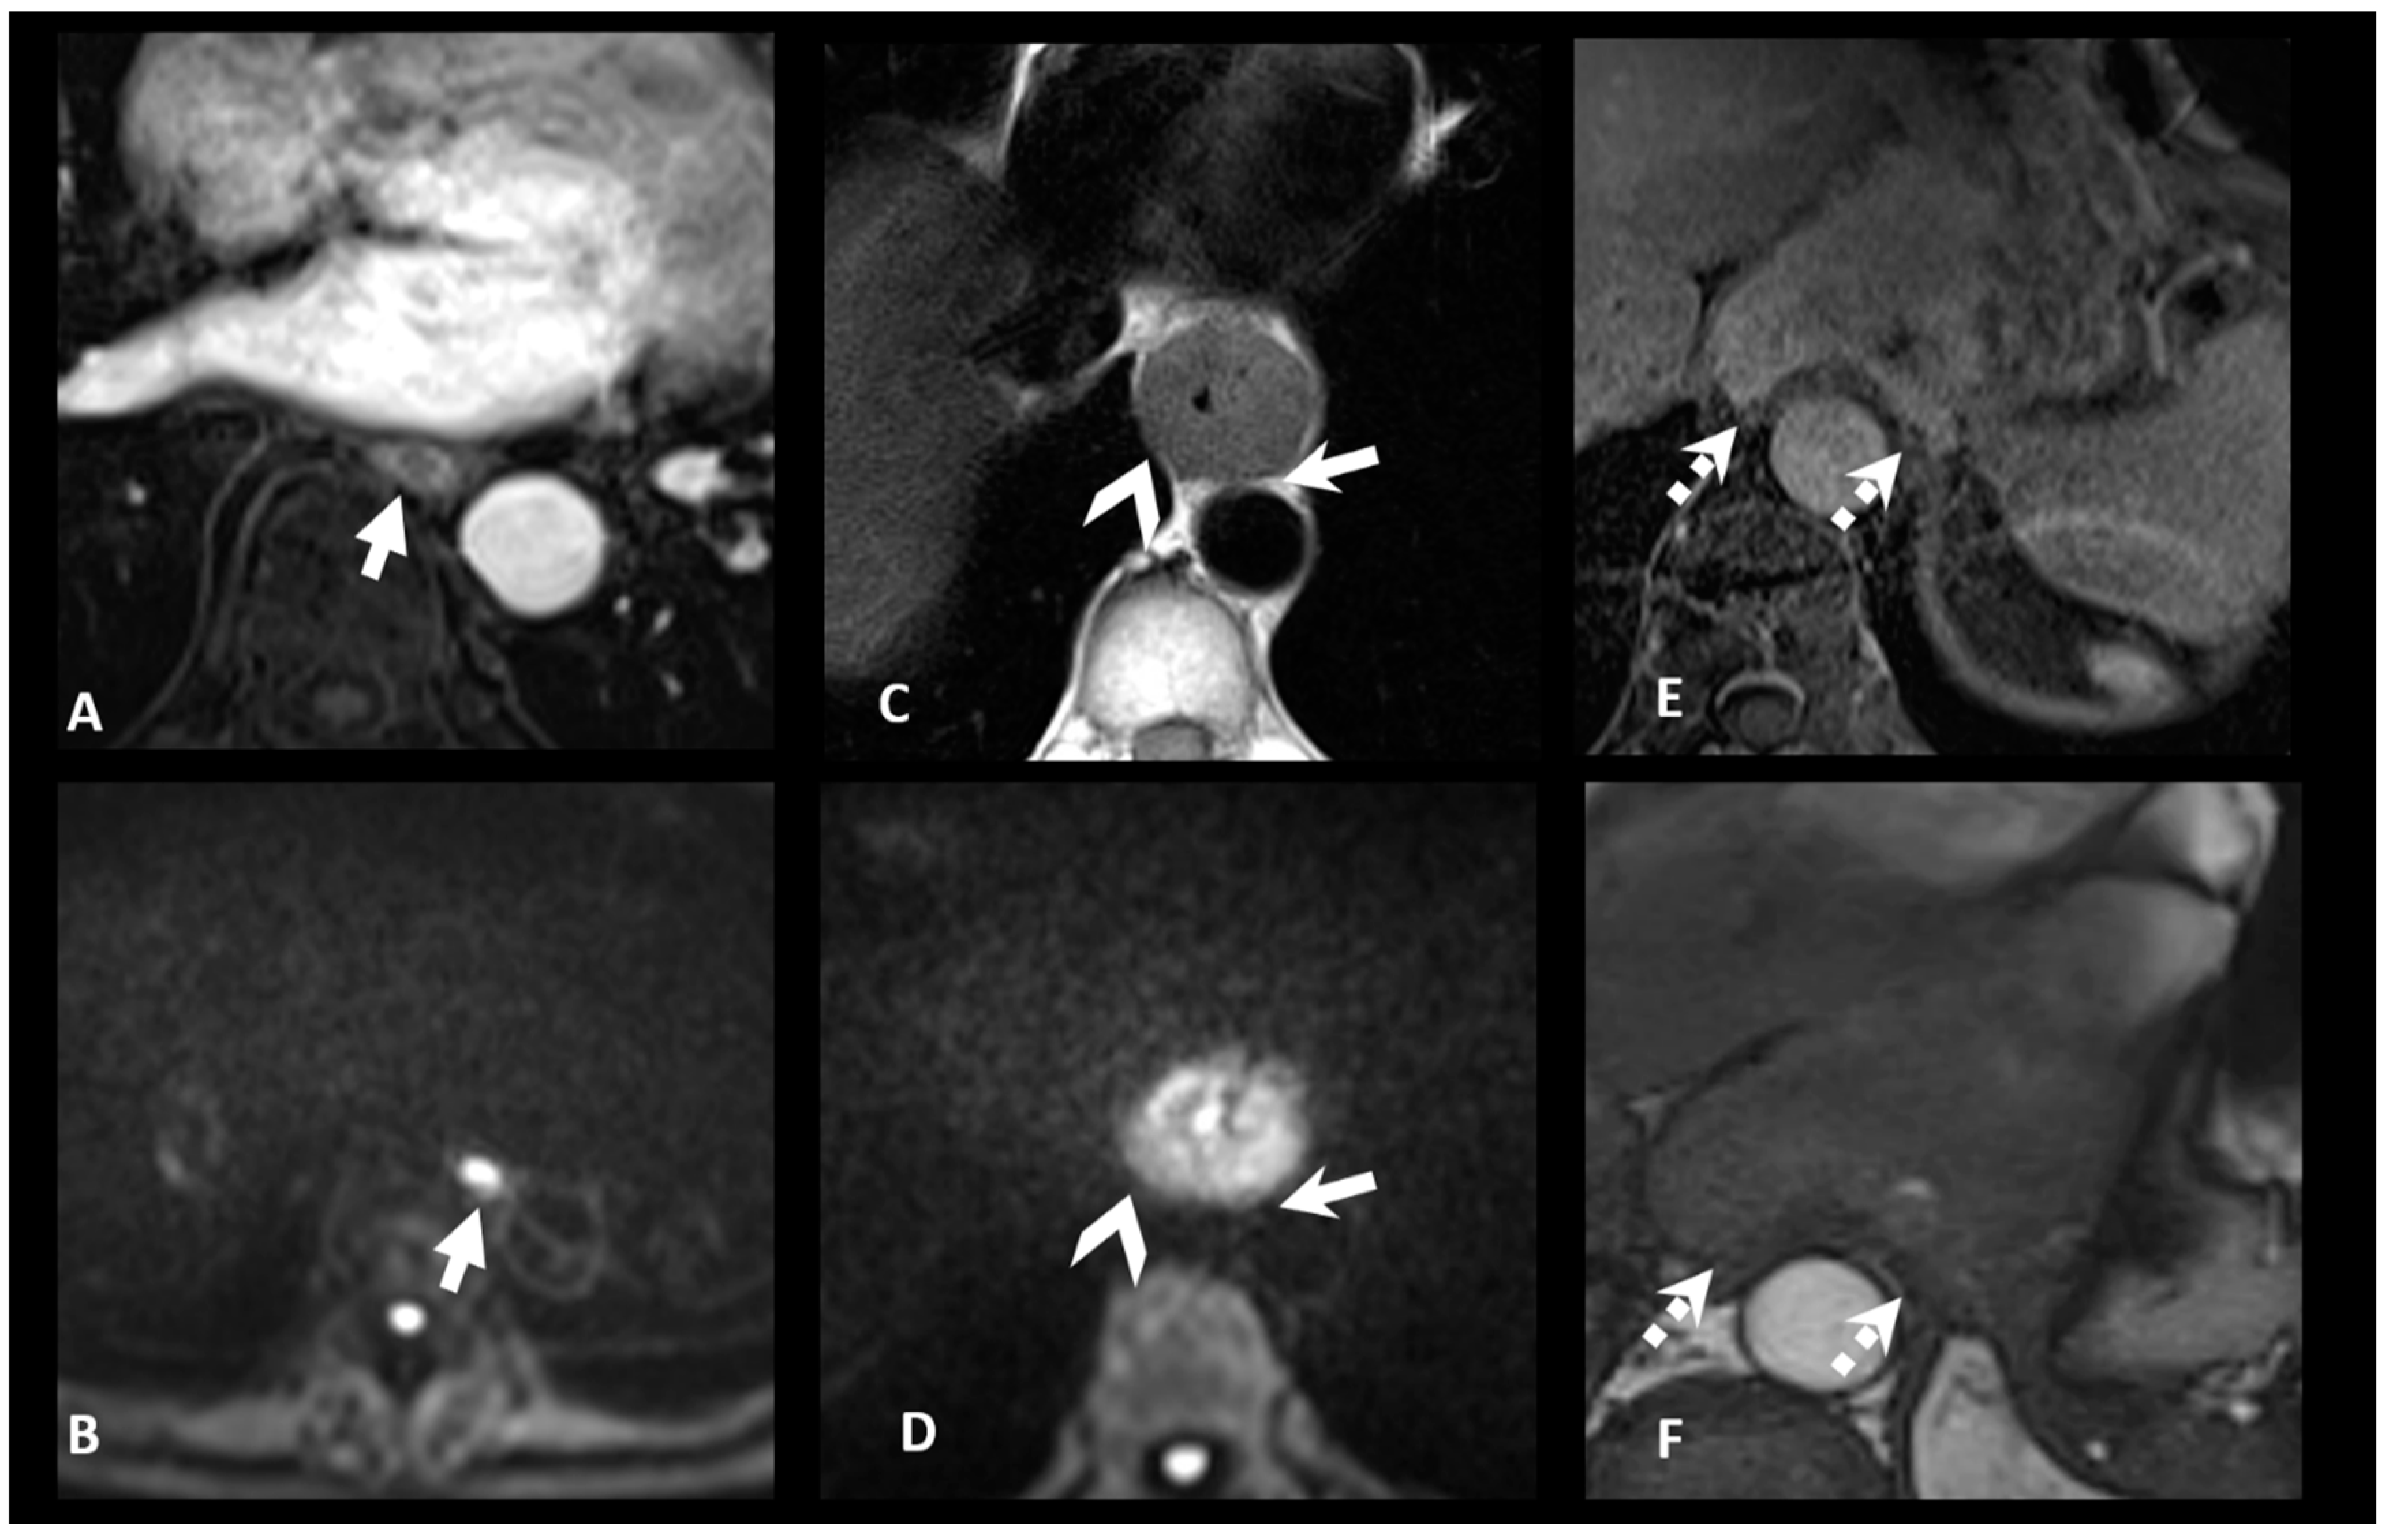

3.2. N Staging

| N+: Regional lymph nodes metastasis | MRI-N+: Round, Intermediate to high T2 signal, heterogeneous T1 Gd, >5 mm small axe |